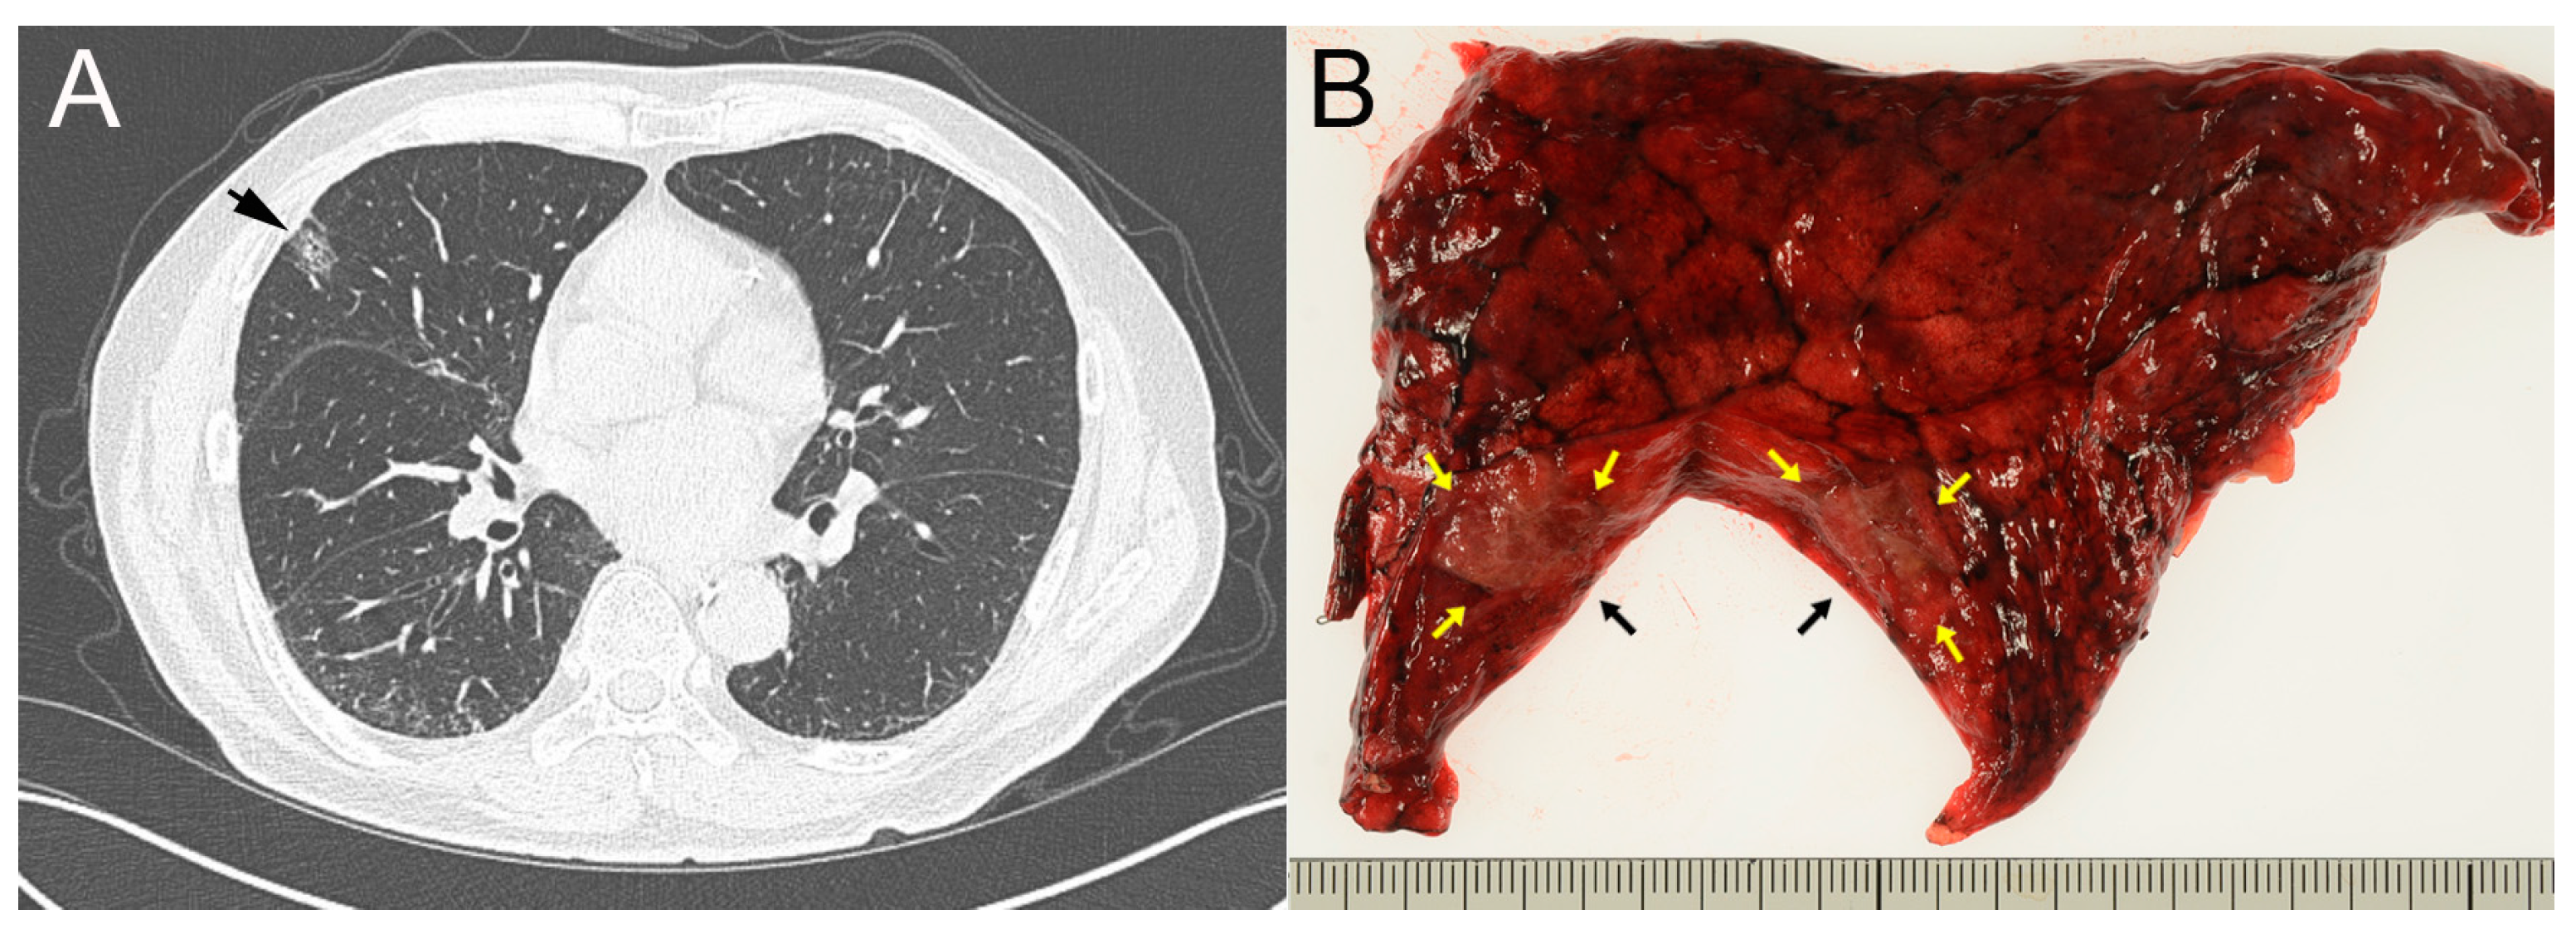

A 74-year-old Japanese man, under treatment of alcoholic liver cirrhosis, hepatocellular carcinoma and chronic renal failure, underwent a screening CT and a subsolid nodule with a diameter of 15 mm was incidentally pointed out in the right upper lobe of the lung (Figure 1A). He had no history of smoking. The tumor markers on admission were as follows: CEA 7.3 ng/mL (Reference, 0.0–5.0), CA19-9 < 2.0 U/mL (0.0–37.0), SCC 1.0 ng/mL (0.0–1.5), NSE 7.9 ng/mL (0.0–16.3), CYFR 1.3 ng/mL (0.0–3.5), Pro GRP 45.8 pg/mL (0.0–80.9).

Figure 1.

(A) A 15 mm-sized subsolid nodule was observed in the periphery of the upper lobe, S3, of the right lung (arrow). (B) Cut surface of the resected lung specimen. A grayish-brown nodule, 10 × 7 mm in size, was observed (arrows).

Early lung cancer was suspected, and a wedge resection was performed by video-assisted thoracoscopic surgery (VATS). The wedge resection sample, 9 × 5 cm in size, was submitted and a grayish-brown tumor sized 10 × 7 mm was observed on the cut surface (Figure 1B). Intraoperative FSD revealed mildly thickened alveolar septa, lined with a single layer of cuboidal or low columnar epithelium with mildly enlarged nuclei, which pathologists interpreted as reactive type 2 pneumocyte (Figure 2A,B). Cytological and structural atypia was modest, and stromal invasion was not observed. In addition to stromal fibrosis, process formation surrounded by many foamy macrophages was observed in the alveolar duct (Figure 2C,D). Nuclear inclusion in the epithelial cells and mucinous background were not evident in the FSD. Simultaneously performed TIC revealed mucinous background with a lot of macrophages and nuclear inclusion in the epithelial cells (Figure 3A–D). However, two pathologists made a tentative diagnosis of focal organizing or non-specific interstitial pneumonia through discussion, because nuclear inclusion is occasionally observed in non-neoplastic lung tissue (Figure 4A–D). No atypical tissue was observed at the resection margin. As a result, an additional lobectomy and lymphadenectomy were not performed.